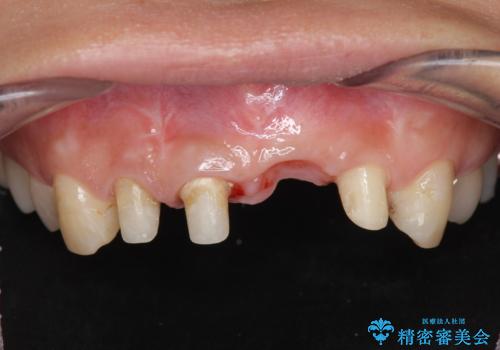

左側の前歯には他院で埋入されたポジションの悪いインプラント補綴により歯冠長の長いクラウンが装着されており、感染による排膿も認められこのまま審美性を改善するのは難しい状態です。

感染したインプラントからは排膿が間欠的に認められ、掻爬・除去が検討されうるような状況でした。

より審美的な改善を強く求められたため、インプラントを除去し可及的に欠損部顎堤を増大したのちブリッジによる審美改善を行いました。